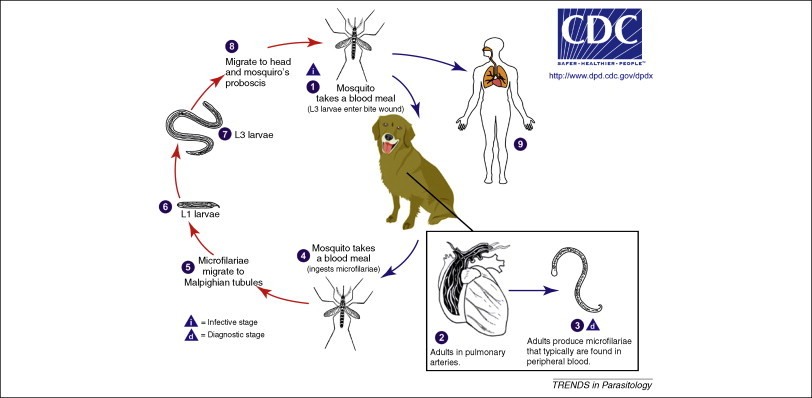

Hogy megértsük, hogy milyen szert, mikor és miért alkalmazunk kutyáinknál, érdemes ismernünk a szívféreg fejlődési ciklusát.

Ezen féregfaj természetes gazdája a kutya. A fertőzött kutyában élősködő ivarérett nőstény féreg (amennyiben kifejlett hím is van az adott gazdában) 0,3 mm nagyságú lárvákat, úgynevezett mikrofiláriákat bocsát a véráramba. Ezek önmagukban tüneteket nem okoznak, a kutyában közvetlenül tovább nem fejlődnek, vagyis nem lesz belőlük kifejlett féreg. Amennyiben azonban a fertőzött állaton egy szúnyog vért szív, és közben mikrofiláriákat vesz fel, a szúnyog szervezetében a lárvák fejlődésnek indulnak. Számukra optimális hőmérsékleten két hét alatt két vedlésen esnek át, és fertőzőképes, harmadik stádiumú lárvákká fejlődnek.

Ezt követően, ha a szúnyog vért szív egy újabb gazdán (vagy akár ugyanazon), ezek a lárvák a szúnyog szájszervein keresztül átvándorolnak a gazda szervezetébe. A bőr alatti szövetekben, vagy az izomszövetben 2-3 nap alatt negyedik, majd két-három (vagy több) hónap után ötödik stádiumú lárvává, úgynevezett preadultokká alakulnak. Ez utóbbiak a vérárammal a szívbe és a tüdőartériákba jutnak, és ott újabb 3 hónap alatt ivaréretté válnak, szaporodni kezdenek. A szúnyogcsípéstől az ivaréretté válásig átlagosan 6-9 hónap telik el. A kifejlett férgek 5-7, vagy akár több évig is élhetnek.

A kifejlett férgek elsősorban a tüdő verőereiben élnek. Nagyszámú féreg esetén a szív jobb kamrájában, a jobb pitvarban, és esetleg az ide a test felől vért szállító gyűjtőérben is találkozhatunk velük.

A fejlődési ciklusban kulcsszerepet játszik a szúnyog. Szúnyog nélkül a mikrofiláriák fejlődése megakad. A betegség kutyáról kutyára közvetlen érintkezéssel nem terjed, a vemhes szuka azonban átadhatja kölykeinek a parazitát.

Kép: cell.com